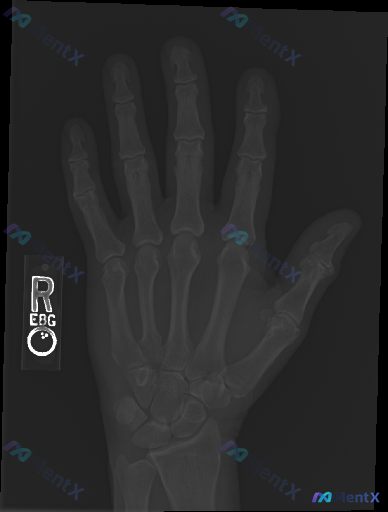

整理到一个临床与影像结合的手部病例资料,想和大家讨论一下思路: --- 影像资料:右侧手部正位X光片 影像学观察: - 骨骼:各掌骨、指骨、腕骨骨皮质连续,未见明确骨折线、成角或阶梯状改变;骨小梁排列规律,未见局部密度异常减低或硬化区;第一掌骨基底部、第五掌骨颈等特定部位也未见典型骨折表现。 - 关...

整理到一个值得讨论的影像相关情况: 病例背景 一份右手正位X光片,常规影像学评估结果如下: - 各指骨、掌骨、腕骨骨皮质连续性未见明显中断,无明确骨折线、隐匿性骨折征象或骨膜反应; - 各掌指、指间关节及腕骨间关节间隙基本正常,对位良好,无脱位半脱位; - 骨质密度分布均匀,未见明显骨质疏松、骨质硬...

整理了一份右手指部的影像+临床分析资料,觉得很适合讨论「影像阴性≠临床没事」的情况。 先给出影像的客观结论: 这份是右手指斜位X光片,影像科报告的描述是: - 各段骨皮质连续,未见明显骨折线或脱位征象 - 关节对位正常,关节间隙清晰 - 骨质密度均匀,未见骨侵蚀或增生 - 软组织轮廓自然,未见明显高...